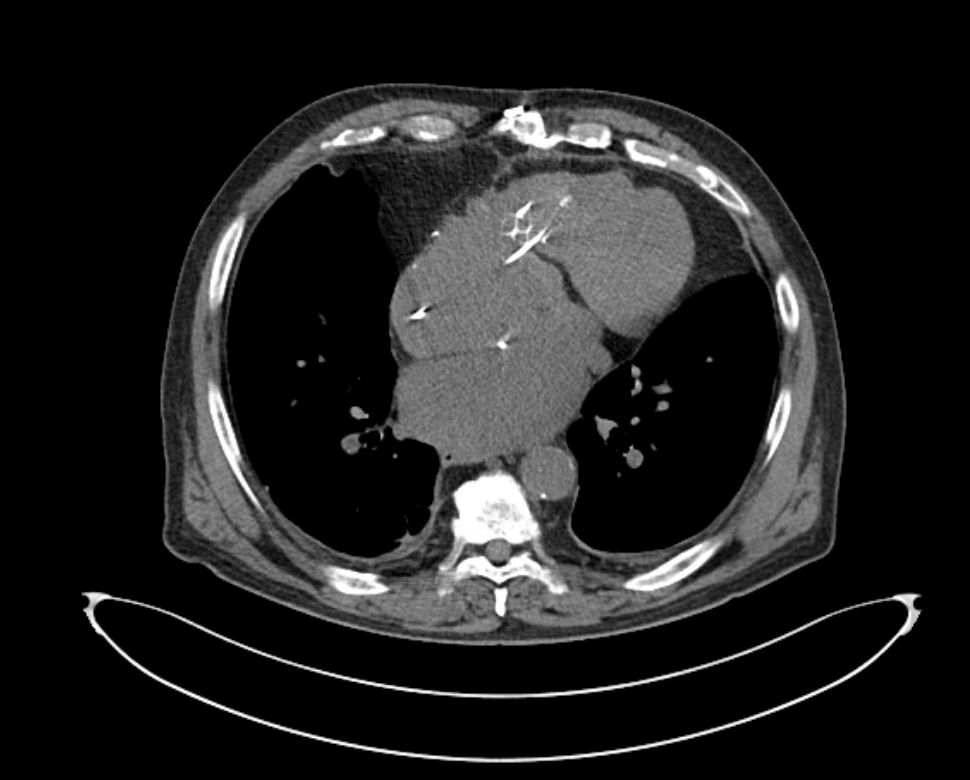

NI DCM. EF 25%. #ECG #EPeeps #CardioTwitter @AdolfoFontenla @jvillacastin @ALFIEEP1 @EF_Cardiaca @Ed_Gerst @Arritmias_HRC @FellowEP @syamkumarmd @DrRoderickTung @ArritmiasHUSC